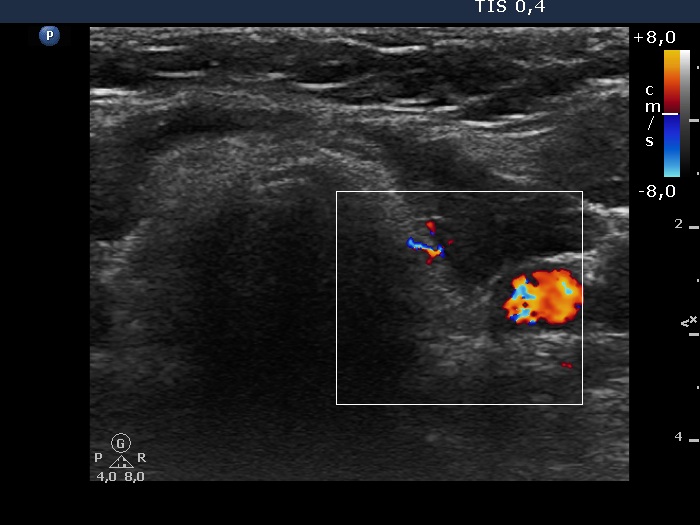

Consecutive patients with Hashimoto's thyroiditis - Case 6. (ultrasonographic picture 7)

Left lobe, horizontal scan, color Doppler mode. The vascularization is decreased, non-specific.